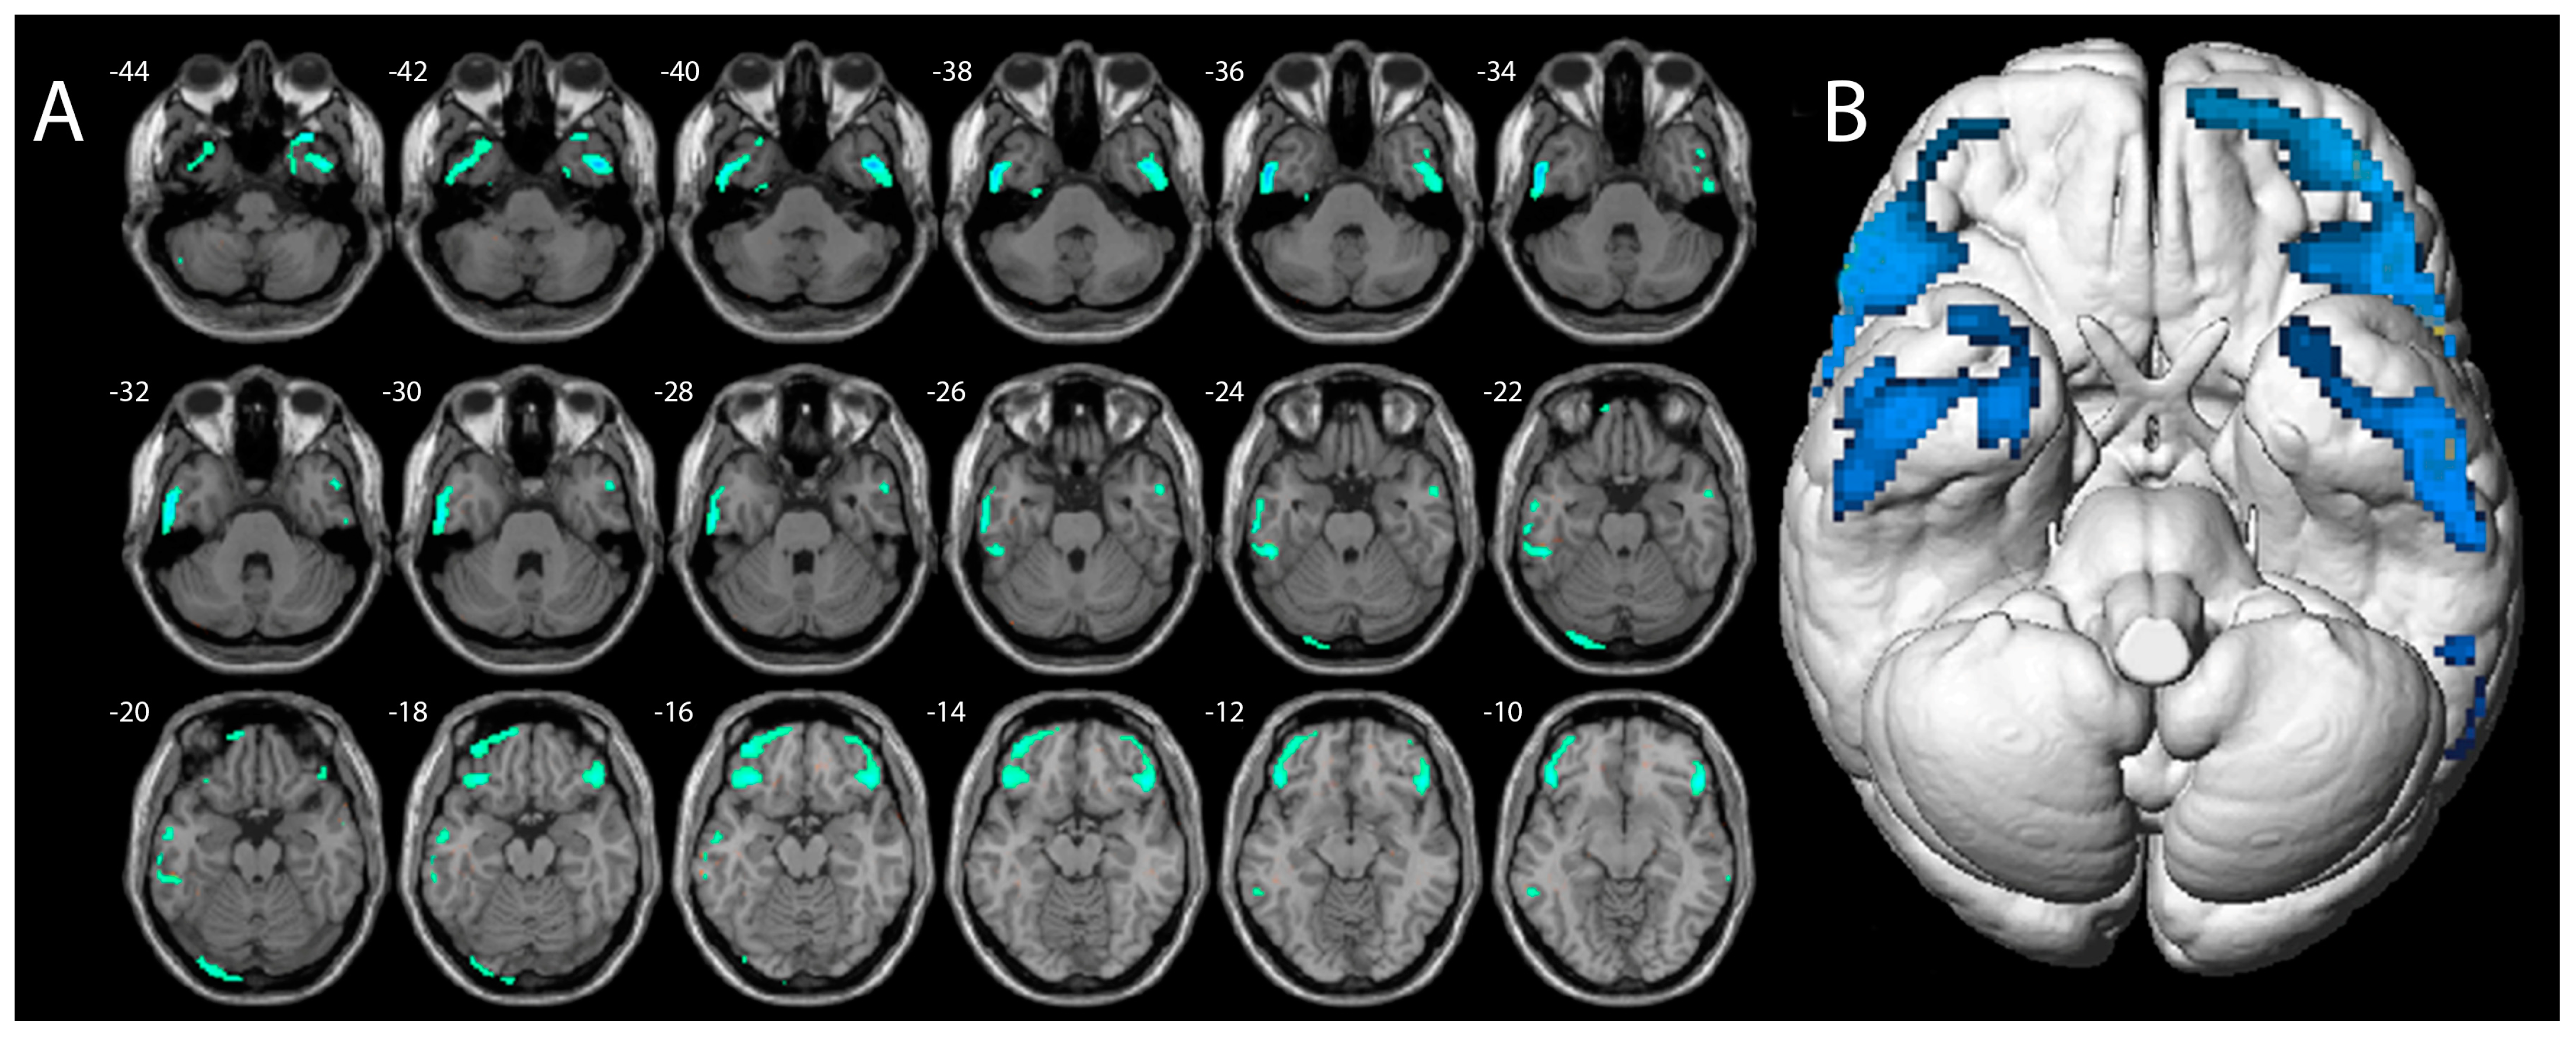

- Moccia, L.; Tofani, A.; Mazza, M.; Covino, M.; Martinotti, G.; Schifano, F.; Janiri, L.; Di Nicola, M. Dorsolateral Prefrontal Cortex Impairment in Methoxetamine-Induced Psychosis: An 18F-FDG PET/CT Case Study. J. Psychoact. Drugs 2019, 51, 254–259. [Google Scholar] [CrossRef] [PubMed]

- Murnane, K.S.; Edinoff, A.N.; Cornett, E.M.; Kaye, A.D. Updated Perspectives on the Neurobiology of Substance Use Disorders Using Neuroimaging. Subst. Abuse Rehabil. 2023, 14, 99–111. [Google Scholar] [CrossRef]

- Jodo, E. The role of the hippocampo-prefrontal cortex system in phencyclidine-induced psychosis: A model for schizophrenia. J. Physiol. Paris 2013, 107, 434–440. [Google Scholar] [CrossRef] [PubMed]

- Horacek, J.; Dockery, C.; Kopecek, M.; Spaniel, F.; Novak, T.; Tislerova, B.; Klirova, M.; Palenicek, T.; Höschl, C. Regional brain metabolism as the predictor of performance on the Trail Making Test in schizophrenia. A 18FDG PET covariation study. Neuroendocrinol. Lett. 2006, 27, 587–594. [Google Scholar] [PubMed]

- Moreno-López, L.; Stamatakis, E.A.; Fernández-Serrano, M.J.; Gómez-Río, M.; Rodríguez-Fernández, A.; Pérez-García, M.; Verdejo-García, A. Neural correlates of hot and cold executive functions in polysubstance addiction: Association between neuropsychological performance and resting brain metabolism as measured by positron emission tomography. Psychiatry Res. 2012, 203, 214–221. [Google Scholar] [CrossRef] [PubMed]